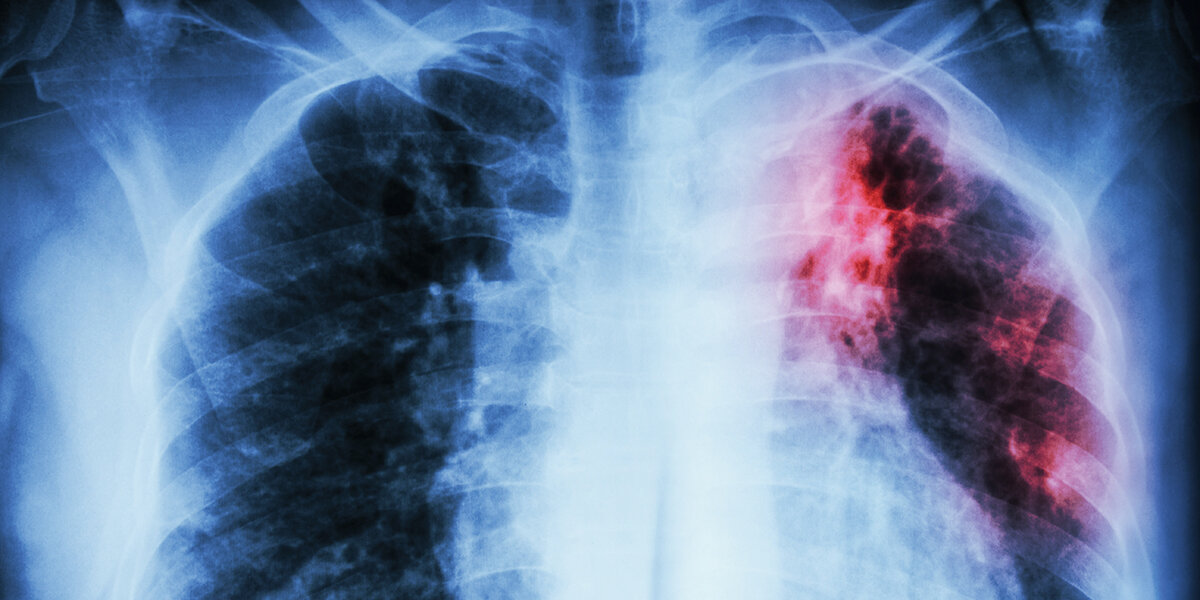

Сегодня очень многие люди болеют туберкулезом! Еще 100 лет назад это заболевание считалось не излечимым, и всегда заболевшего человека ожидал летальный исход. Но туберкулез лечится и предупреждается. Детям еще в роддоме делают прививку и контролируют соблюдение прививочного графика на протяжении всей учебы ребенка. Туберкулез – это инфекционное заболевание, передающееся воздушно-капельным путем, поражающее в основном (в 90% случаев заболеваемости) легкие. Возбудителем туберкулеза является палочка Коха, получившая свое название в честь имени ученого. Этот микроорганизм очень устойчив к окружающей среде. Известны случаи, когда палочка Коха оставалась живой через тысячелетия. Например, в мумифицированных костях фараонов находили живые туберкулезные палочки. В современной жизни все медицинские учреждения при их посещении, все предприятия при трудоустройстве, учебные заведения при поступлении требуют заключение рентгенолога на туберкулез. И все это не спроста. Потому что при раннем в